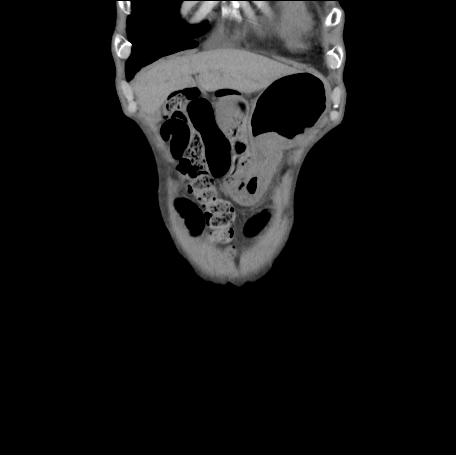

80歳代男性.左鼠径部に違和感と疼痛あり.疼痛が徐々に増強し,下腹部に広がったため当院に救急搬送された.

下腹部に自発痛・圧痛あり.反跳痛なし.左鼠径部に3 cm程の隆起あり.

Q1:単純CT(図1,2)の異常所見は?

図2 腹部単純CT(冠状断像)

誌面掲載画像は赤枠で示す